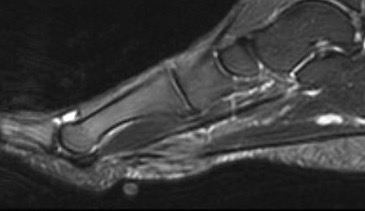

MRI

Focal oval shaped lesions within the plantar fascia